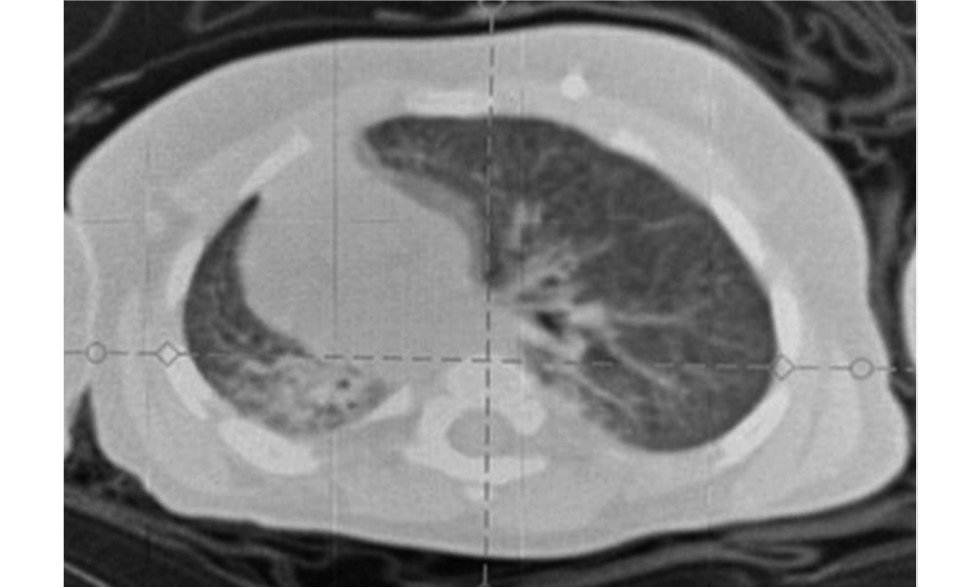

С целью исключения врождённых пороков развития лёгких — подковообразное лёгкое, трахеобронхомаляция, лобарная эмфизема, гипоплазия лёгкого, бронхогенная киста, объёмное образование в грудной полости — в возрасте 1,5 мес. была выполнена мультиспиральная компьютерная томография-ангиография (МСКТА) органов грудной полости (рис. 6).

Рис. 6. Мультиспиральная компьютерная томография-ангиография органов грудной полости на 1,5 мес. жизни: тотальный ателектаз правого лёгкого (a — аксиальная реконструкция, b — фронтальная реконструкция; c — сагиттальная реконструкция).

Fig. 6. Multispiral computed tomography-angiography of the chest organs at 1.5 months of life: total atelectasis of the right lung (a — axial reconstruction, b — frontal reconstruction; c — sagittal reconstruction).

Выявлена картина ТАПЛ с компенсаторным вздутием ткани левого лёгкого и формированием передней парамедиастинальной грыжи. Органы средостения резко смещены вправо. Обнаружены признаки дистонии трахеи, а также деформация и обструкция устьев обоих главных бронхов, более выраженная справа. Другие возможные причины хронического ателектаза правого лёгкого — гипоплазия правой лёгочной артерии, нарушение васкуляризации лёгочной ткани правого лёгкого — не обнаружены.